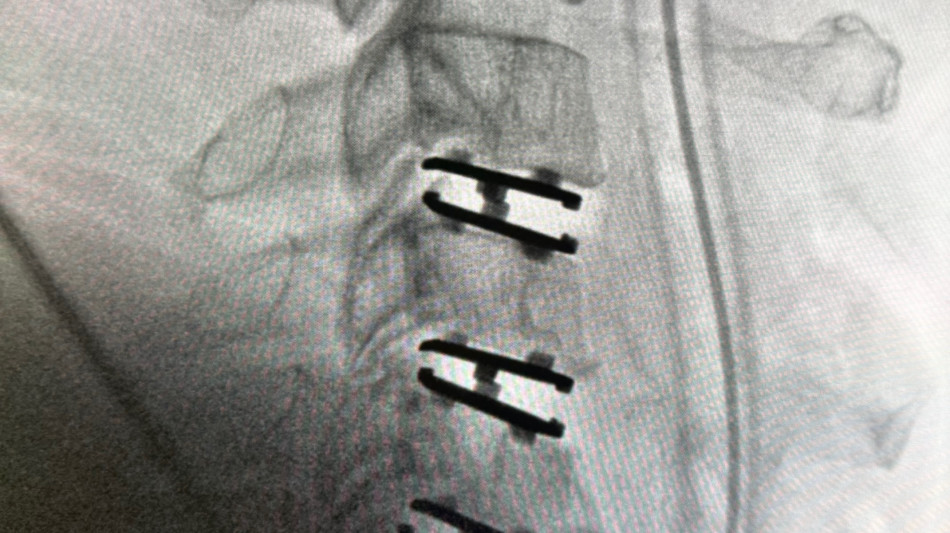

The patient, a 47-year-old man, presented with progressive neck pain, arm pain, and weakness in the setting of spinal cord compression and severe nerve root compression with associated bone spur formation. After failing conservative management, the patient was taken to surgery for a three-level cervical disc replacement to decompress the spinal cord, relieve nerve compression, and remove osteophytic pathology.

The Synergy Disc® is a motion-preserving artificial cervical disc developed by Synergy Spine Solutions and engineered with a lordotic polyethylene core designed to maintain and restore physiologic alignment while allowing controlled motion. The Synergy Disc® is the only artificial cervical disc currently available that combines motion preservation with intentional alignment correction in a single device. The device recently demonstrated superiority to anterior cervical discectomy and fusion (ACDF) in a U.S. Investigational Device Exemption (IDE) clinical trial.

The patient is recovering well following surgery with early reduction in pain. Neurologic recovery will be assessed over time as healing progresses.